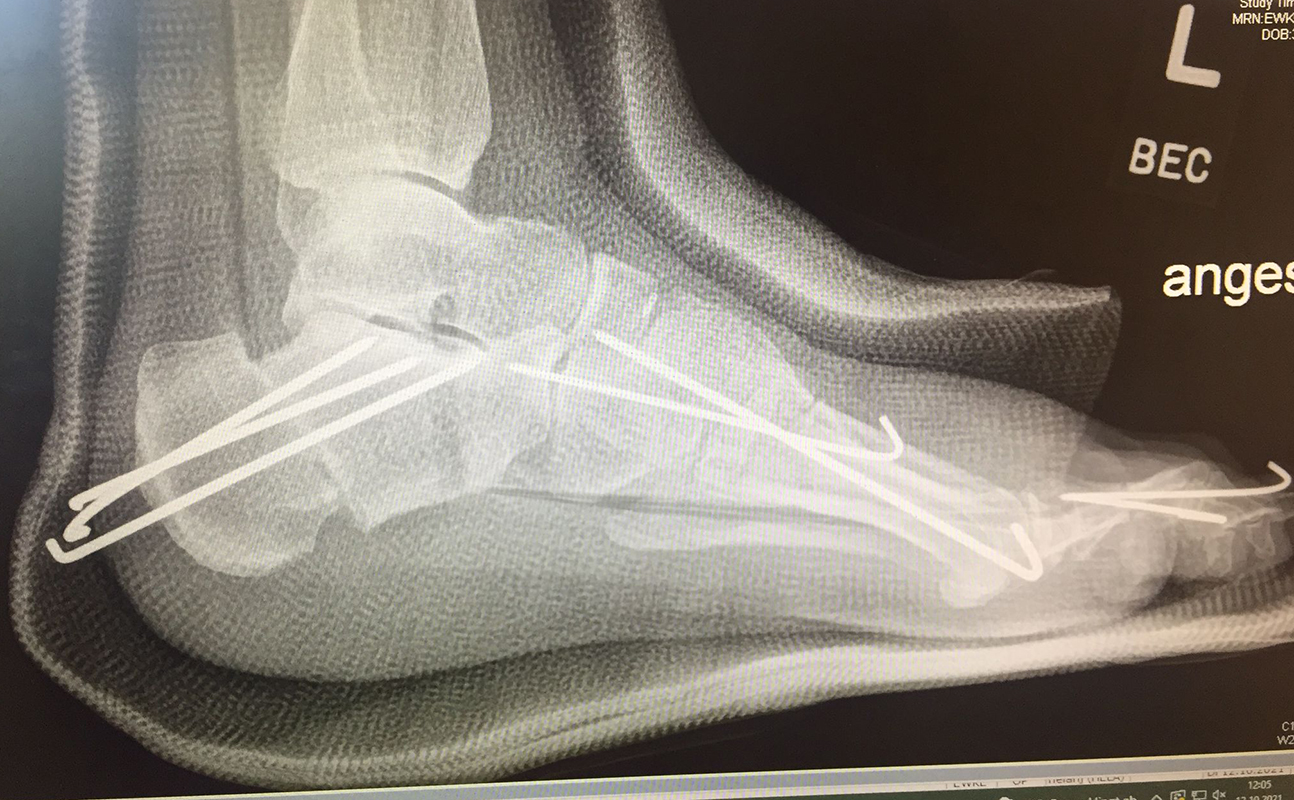

Zusätzlich schränken Wachstumsfugen die Wahl der Osteosynthese ein. Eine die Fuge kreuzende Osteosynthese ist ausschließlich mit Kirschner-Drähten möglich (Abb. 3).

Abb. 3 a-j: Beispiel einer Calcaneusverschiebeosteotomie mit offenen Wachstumsfugen und der entsprechenden Osteosynthese mit Kirschner Drähten. Lokalisation der Osteotomie (a), Lage der Fräse (b-d), Drahtlage mehrere Ansichten (e-h), Heilung der Osteotomie 4 Wochen postoperativ und Entfernung der Drähte (i-j).

Calcaneus-Osteotomie

Die minimalinvasive Calcaneusverschiebeosteotomie bietet eindeutige Vorteile gegenüber dem offenen Verfahren, sodass wir bei Kindern und Jugendlichen nahezu keine offene Verschiebeosteotomie mehr durchführen. Am Calcaneus liegt die offene Wachstumsfuge dorsal. Bei der Durchführung müssen Schenkel der V-förmigen Osteotomie daher etwas steiler angelegt werden, in einem stumpfen Winkel (siehe Abb. 3 a-j). Für die Osteotomie liegen unsere Patienten auf dem Rücken und der BV wird für die exakte Seitaufnahme eingestellt. Der Fuß lagert auf einem hohen OP-Kissen und die Osteotomie kann bequem mit einem langen Kirschner-Draht und einem sterilen Stift angezeichnet werden (Abb. 15).